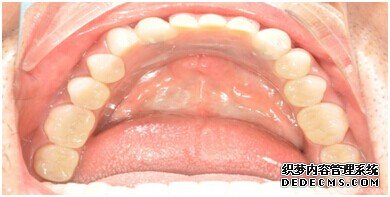

种植设备检查牙齿